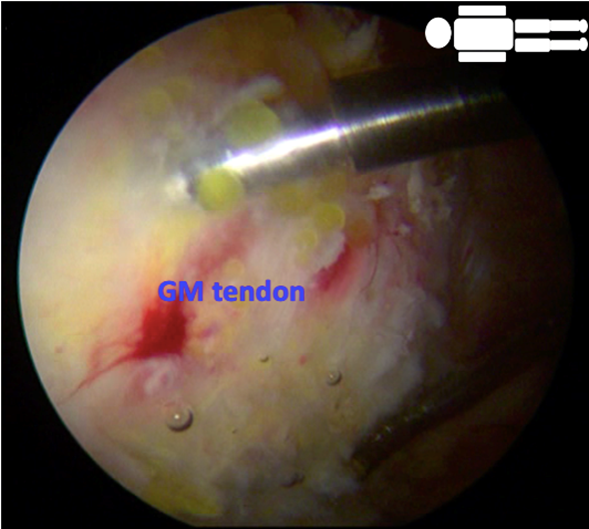

To perform a DPLA portal, a small incision is made in the skin, followed by an opening in the iliotibial band. To avoid the risk of hypothermia, a warmed physiological solution is used during the procedure.26–28 Using endoscopic assistance with 70º optics, a second portal, the PPLA, is made, with a constant flow at a rate of 0.7 liters/minute and a pressure of 40mmHg per bomb. The procedure starts with the hip at a 30º abduction and 0º internal rotation. Then, a partial tenotomy of the distal insertion of the gluteus maximus is performed. The tenotomy is done at the proximal level on the linea aspera, in an anterior-to-posterior direction Figure 2. The tenotomy procedure increases the virtual space available, allowing complete access and reducing pressure on the lateral space. After identifying the greater trochanter, a bursectomy is performed to locate the GM tendon. The tendon shows partial fatty infiltration and tendinopathic appearance on its lateral surface but without tears Figure 3.

Tears are always found on the medial side, which cannot be directly observed. It is explored by palpation to rule out a complete rupture. A third portal is made at the midpoint equidistant between the PPLA and DPLA, the medium posterolateral accessory (MPLA) portal Figure 4. Through this MPLA portal, nine perforations are made in the greater trochanter at the level of the GM insertion with a 2.3mm Bioraptor® anchor drill bit (Smith & Nephew, London, United Kingdom) at a depth of 2.5cm, distributed symmetrically separated approximately 1cm from each other Figure 5. Through the DPLA portal, an 8.25mm cannula specific to the implant is inserted, and then the Regeneten® bioinductive patch loaded is passed. Once the implant has been placed in the desired position, 6 anchors of the Regeneten® system for soft tissues (4.5x6.5mm) are placed through the MPLA portal to set the patch Figure 6. Subsequently, the stability of the implant is confirmed by hip rotation and flexion-extension movements Figure 7. Instruments are removed and the skin is sutured, concluding the surgical procedure.

Figure 5 nine perforations are made in the greater trochanter at the level of the GM insertion with a 2.3mm Bioraptor® anchor drill bit (Smith & Nephew, London, United Kingdom) at a depth of 2.5cm through the MPLA portal, observing with the optics from the PPLA portal.